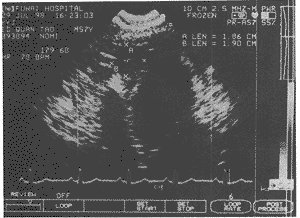

图2 超声心动图心尖四腔切面:舒张期

在瘤体颈部可探及收缩期和舒张期出入瘤体的血流信号,从而证实瘤体有 收缩及舒张功能